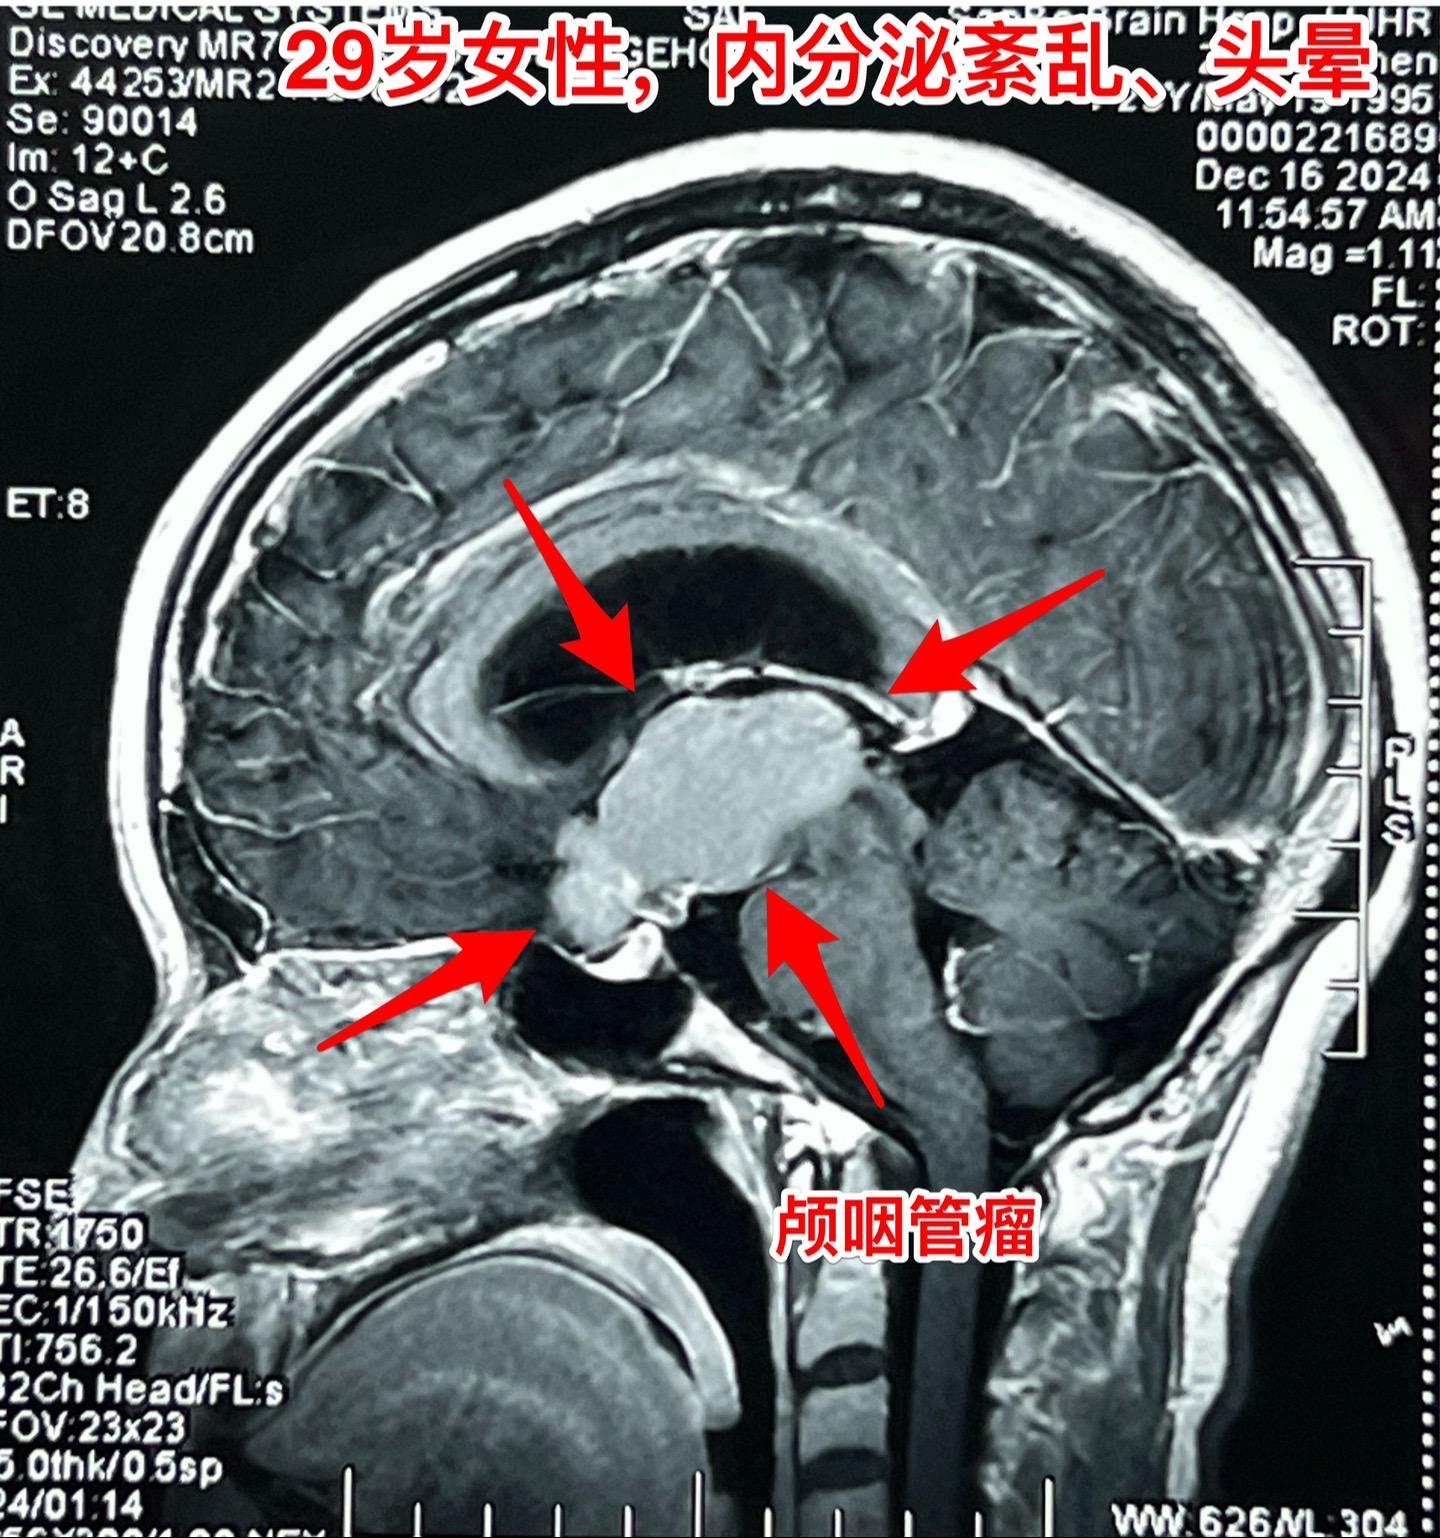

大理市女教师患颅咽管瘤。29岁大理市女老师,因头晕,内分泌功能障碍到医...